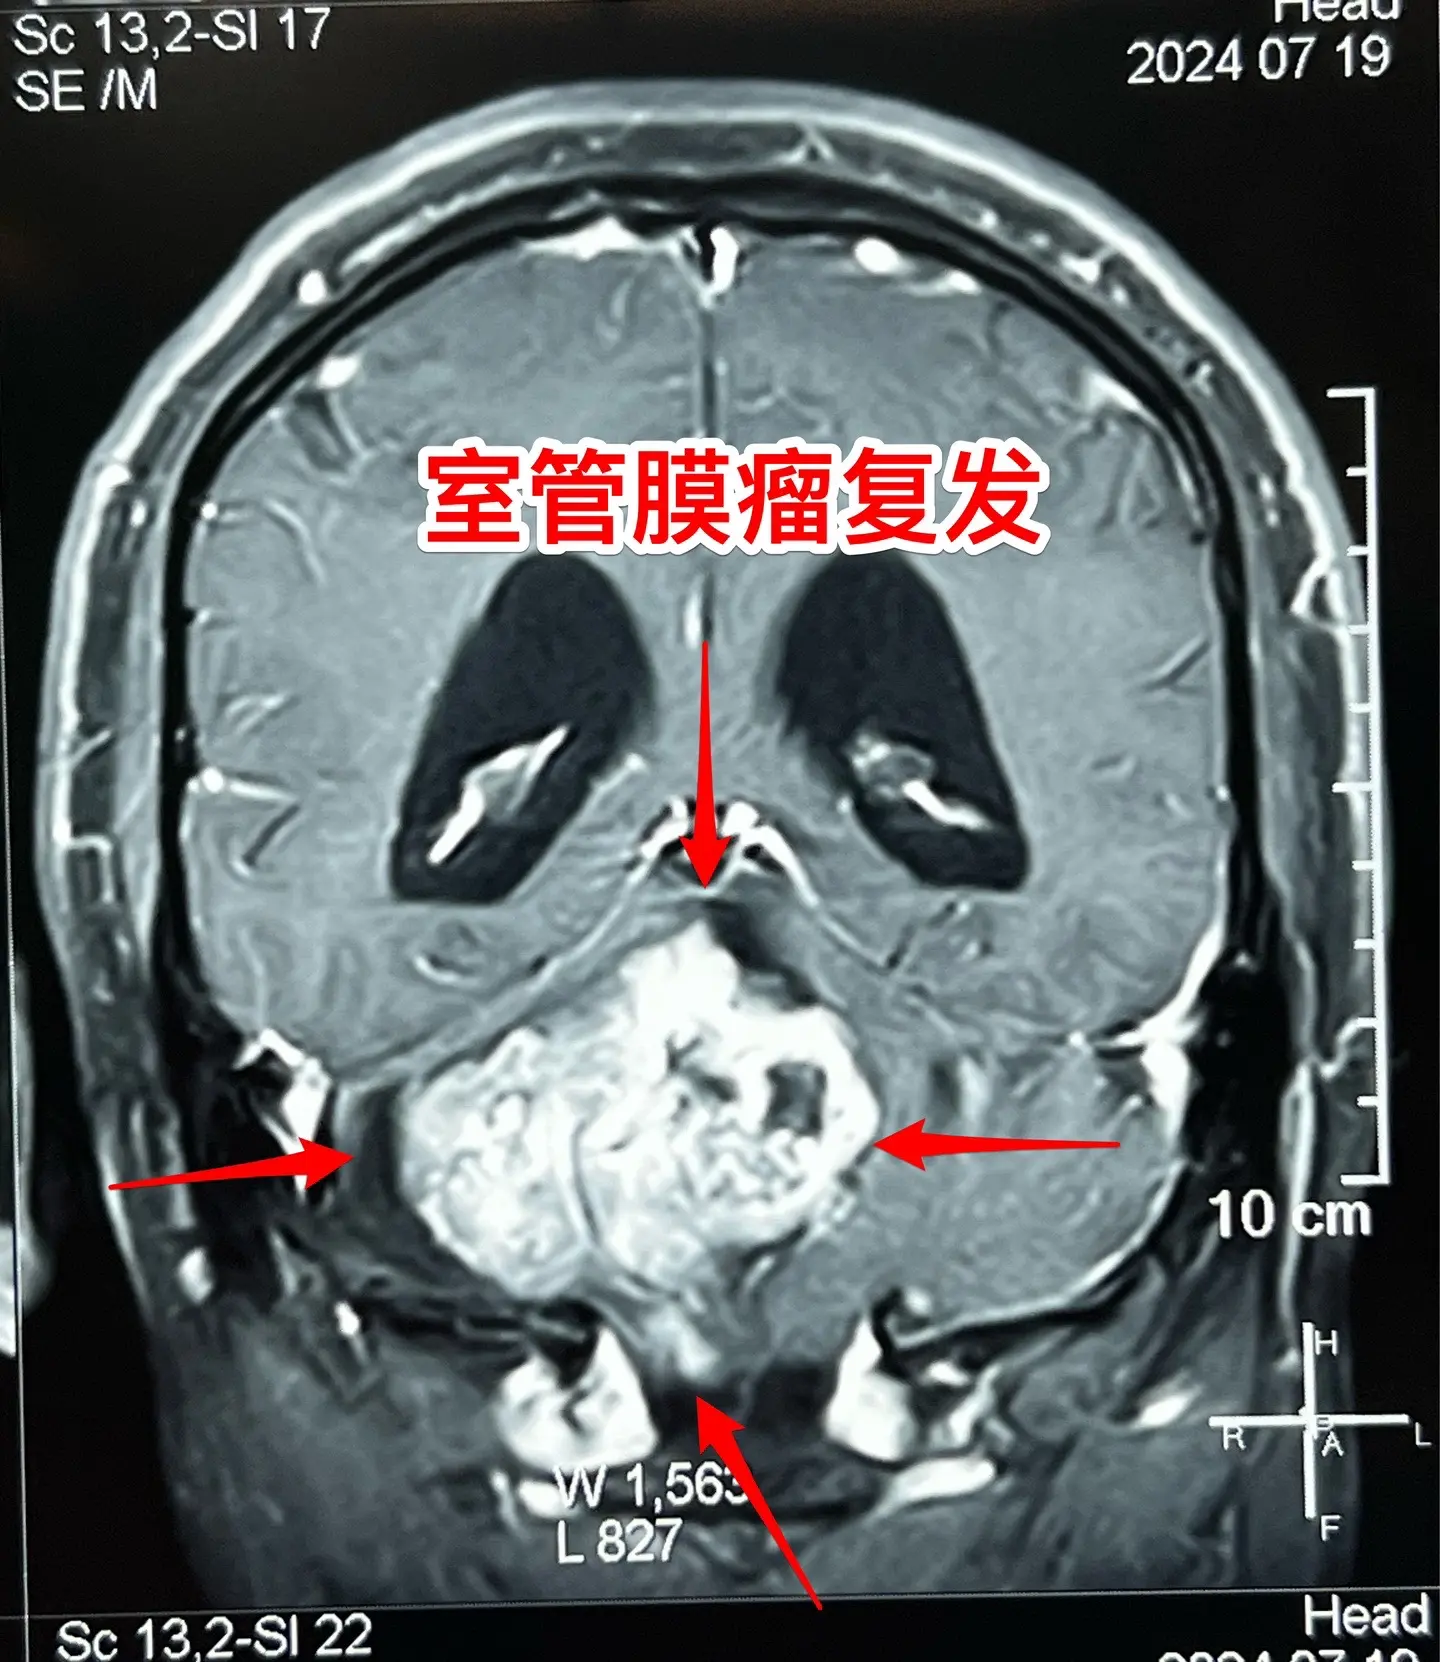

室管膜瘤是良性肿瘤还是恶性肿瘤?41岁的青海省病人,在八年前作过一次开颅手术,现在肿瘤复发了,而且体积很大,脑干实质也受到肿瘤侵蚀,病人有面瘫症状。

室管膜瘤最常见的部位是在小脑,小孩子和大人均可见,即使是完全切除了,想获得治愈是很有难度的,一般认为是恶性肿瘤,化疗、放疗的效果也不确切。